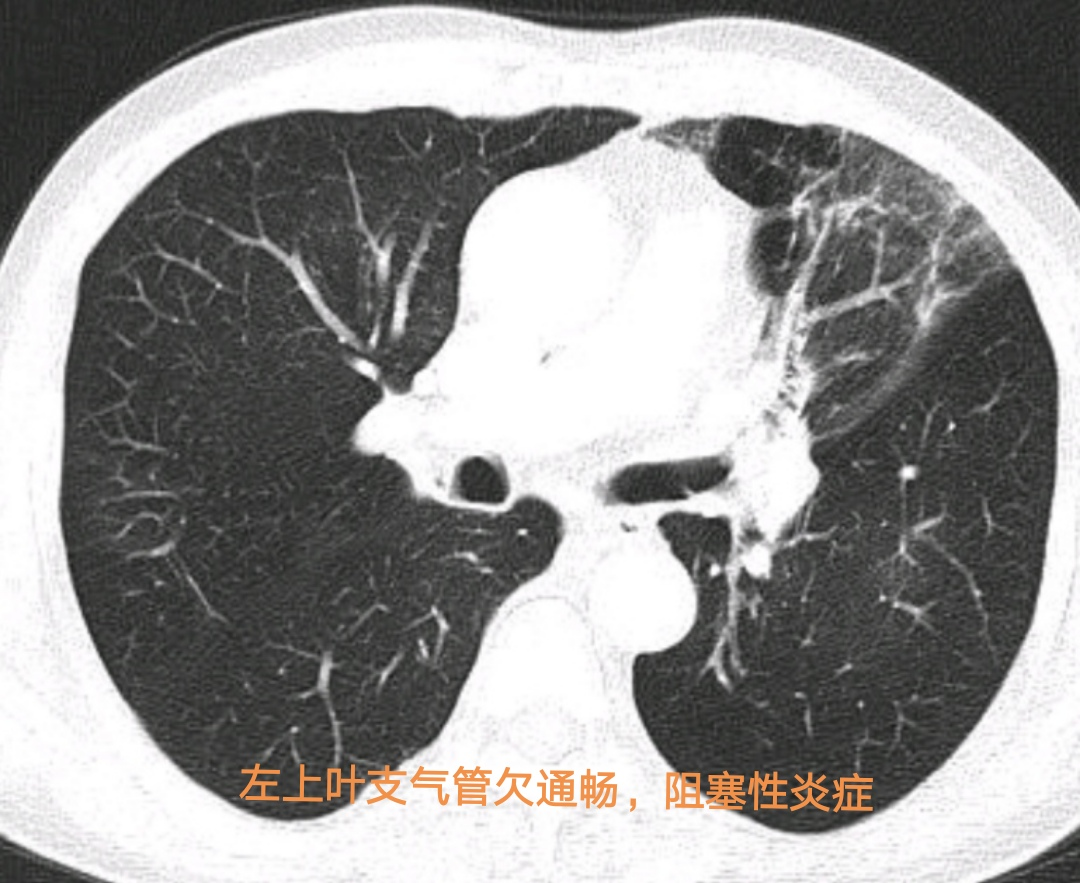

入住医院呼吸与危重症医学科后,经呼吸系疑难病多学科专家会诊,决定为马某行无痛支气管镜检查,以进一步明确病因。支气管镜见左上叶支气管口有新生物,坏死物附着并阻塞管腔,遂行病变活检,以明确诊断。出人意料的是活检病理中看到了少量异物成分。